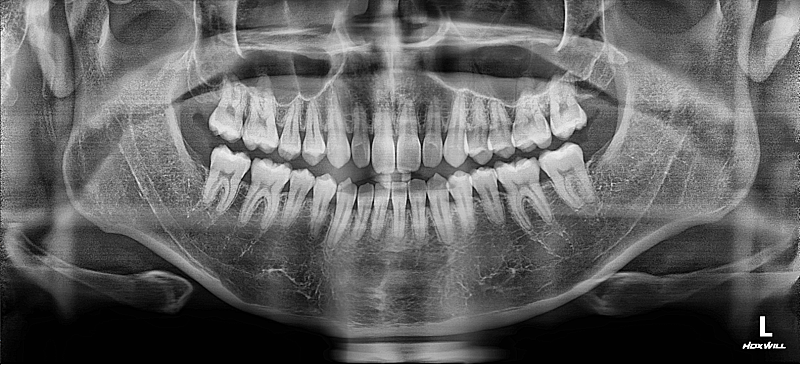

질문4. 제가 가끔 오른쪽 턱관절이 따닥소리나고 통증이 있을때가 있는데 파노라마 사진보면 관절구나 전체적인 턱 상태가 정상일까요?

• 2번 째 사진

4. 현재 상태에서는 정확한 턱관절 상황을 알 수 없으나 사진 상으로 보아서는 크게 문제가 되는 부분은 없습니다. 물론 정확한 판단을 위해서는 ct 및 방사선 뷰가 필요합니다.

-턱관절에 통증이 잇거나 소리가 난다면 턱관절에 문제가 있을수 잇습니다. 통증이 지속되거나 증가된다면 턱관절 검사를 받아보시는게 좋을것같습니다.